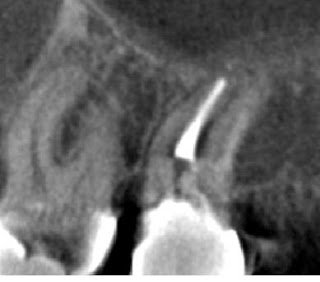

It appeared as if the previous operator perforated during instrumentation, not only between the mesial and distal roots, but also at the apex. In addition to these root perforations, the coronal tooth structure is clearly compromised. The patient was anxious to save the tooth since she invested in root canal treatment and a crown within the last year. I did not feel retreatment would have a good prognosis and recommended extraction. The patient was understandably reluctant about this option, and so I opted to image the tooth with CBCT for more information and better patient education.

In the below left image, I circled the missed DB canal. The below right images (one is reversed, please forgive me) display the missed DB root in the sagittal plane as well as the apical perforation and over enlargement (strip perforation) of the MB root.